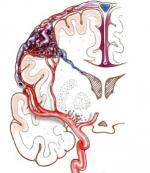

颅内动脉瘤

628健康网为您分享有关颅内动脉瘤的症状,颅内动脉瘤的治疗方法,颅内动脉瘤的预防知识,颅内动脉瘤的症状图片,颅内动脉瘤...

-

大脑大静脉瘤

小儿脑血管畸形

628健康网为您分享有关小儿脑血管畸形的症状,小儿脑血管畸形的治疗方法,小儿脑血管畸形的预防知识,小儿脑血管畸形的症状...

脑动静脉畸形

628健康网为您分享有关脑动静脉畸形的症状,脑动静脉畸形的治疗方法,脑动静脉畸形的预防知识,脑动静脉畸形的症状图片,脑...